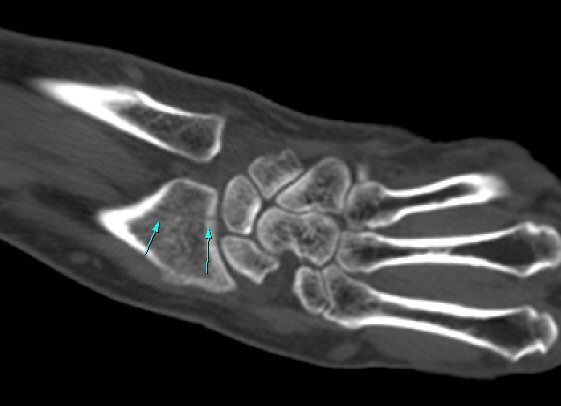

¼Õ¸ñÀÇ Á¾´Ü¸é°Ë»ç¿¡¼­ ¼Õ¸ñ °üÀý³» ºÎÁ¾ÀÌ °üÂûµÊ(»çÁø 1).

ŽÃÍÀÚ¸¦ ¾à°£ ôÃ÷À¸·Î À̵¿ÇÏ´Ï ¿ä°ñ ¸»´Ü¿¡ ÇÇÁú°ñ ¿¬°á¼º ¼Ò½Ç(loss of cotical continuity)ÀÌ °üÂûµÊ(»çÁø 2, 3).